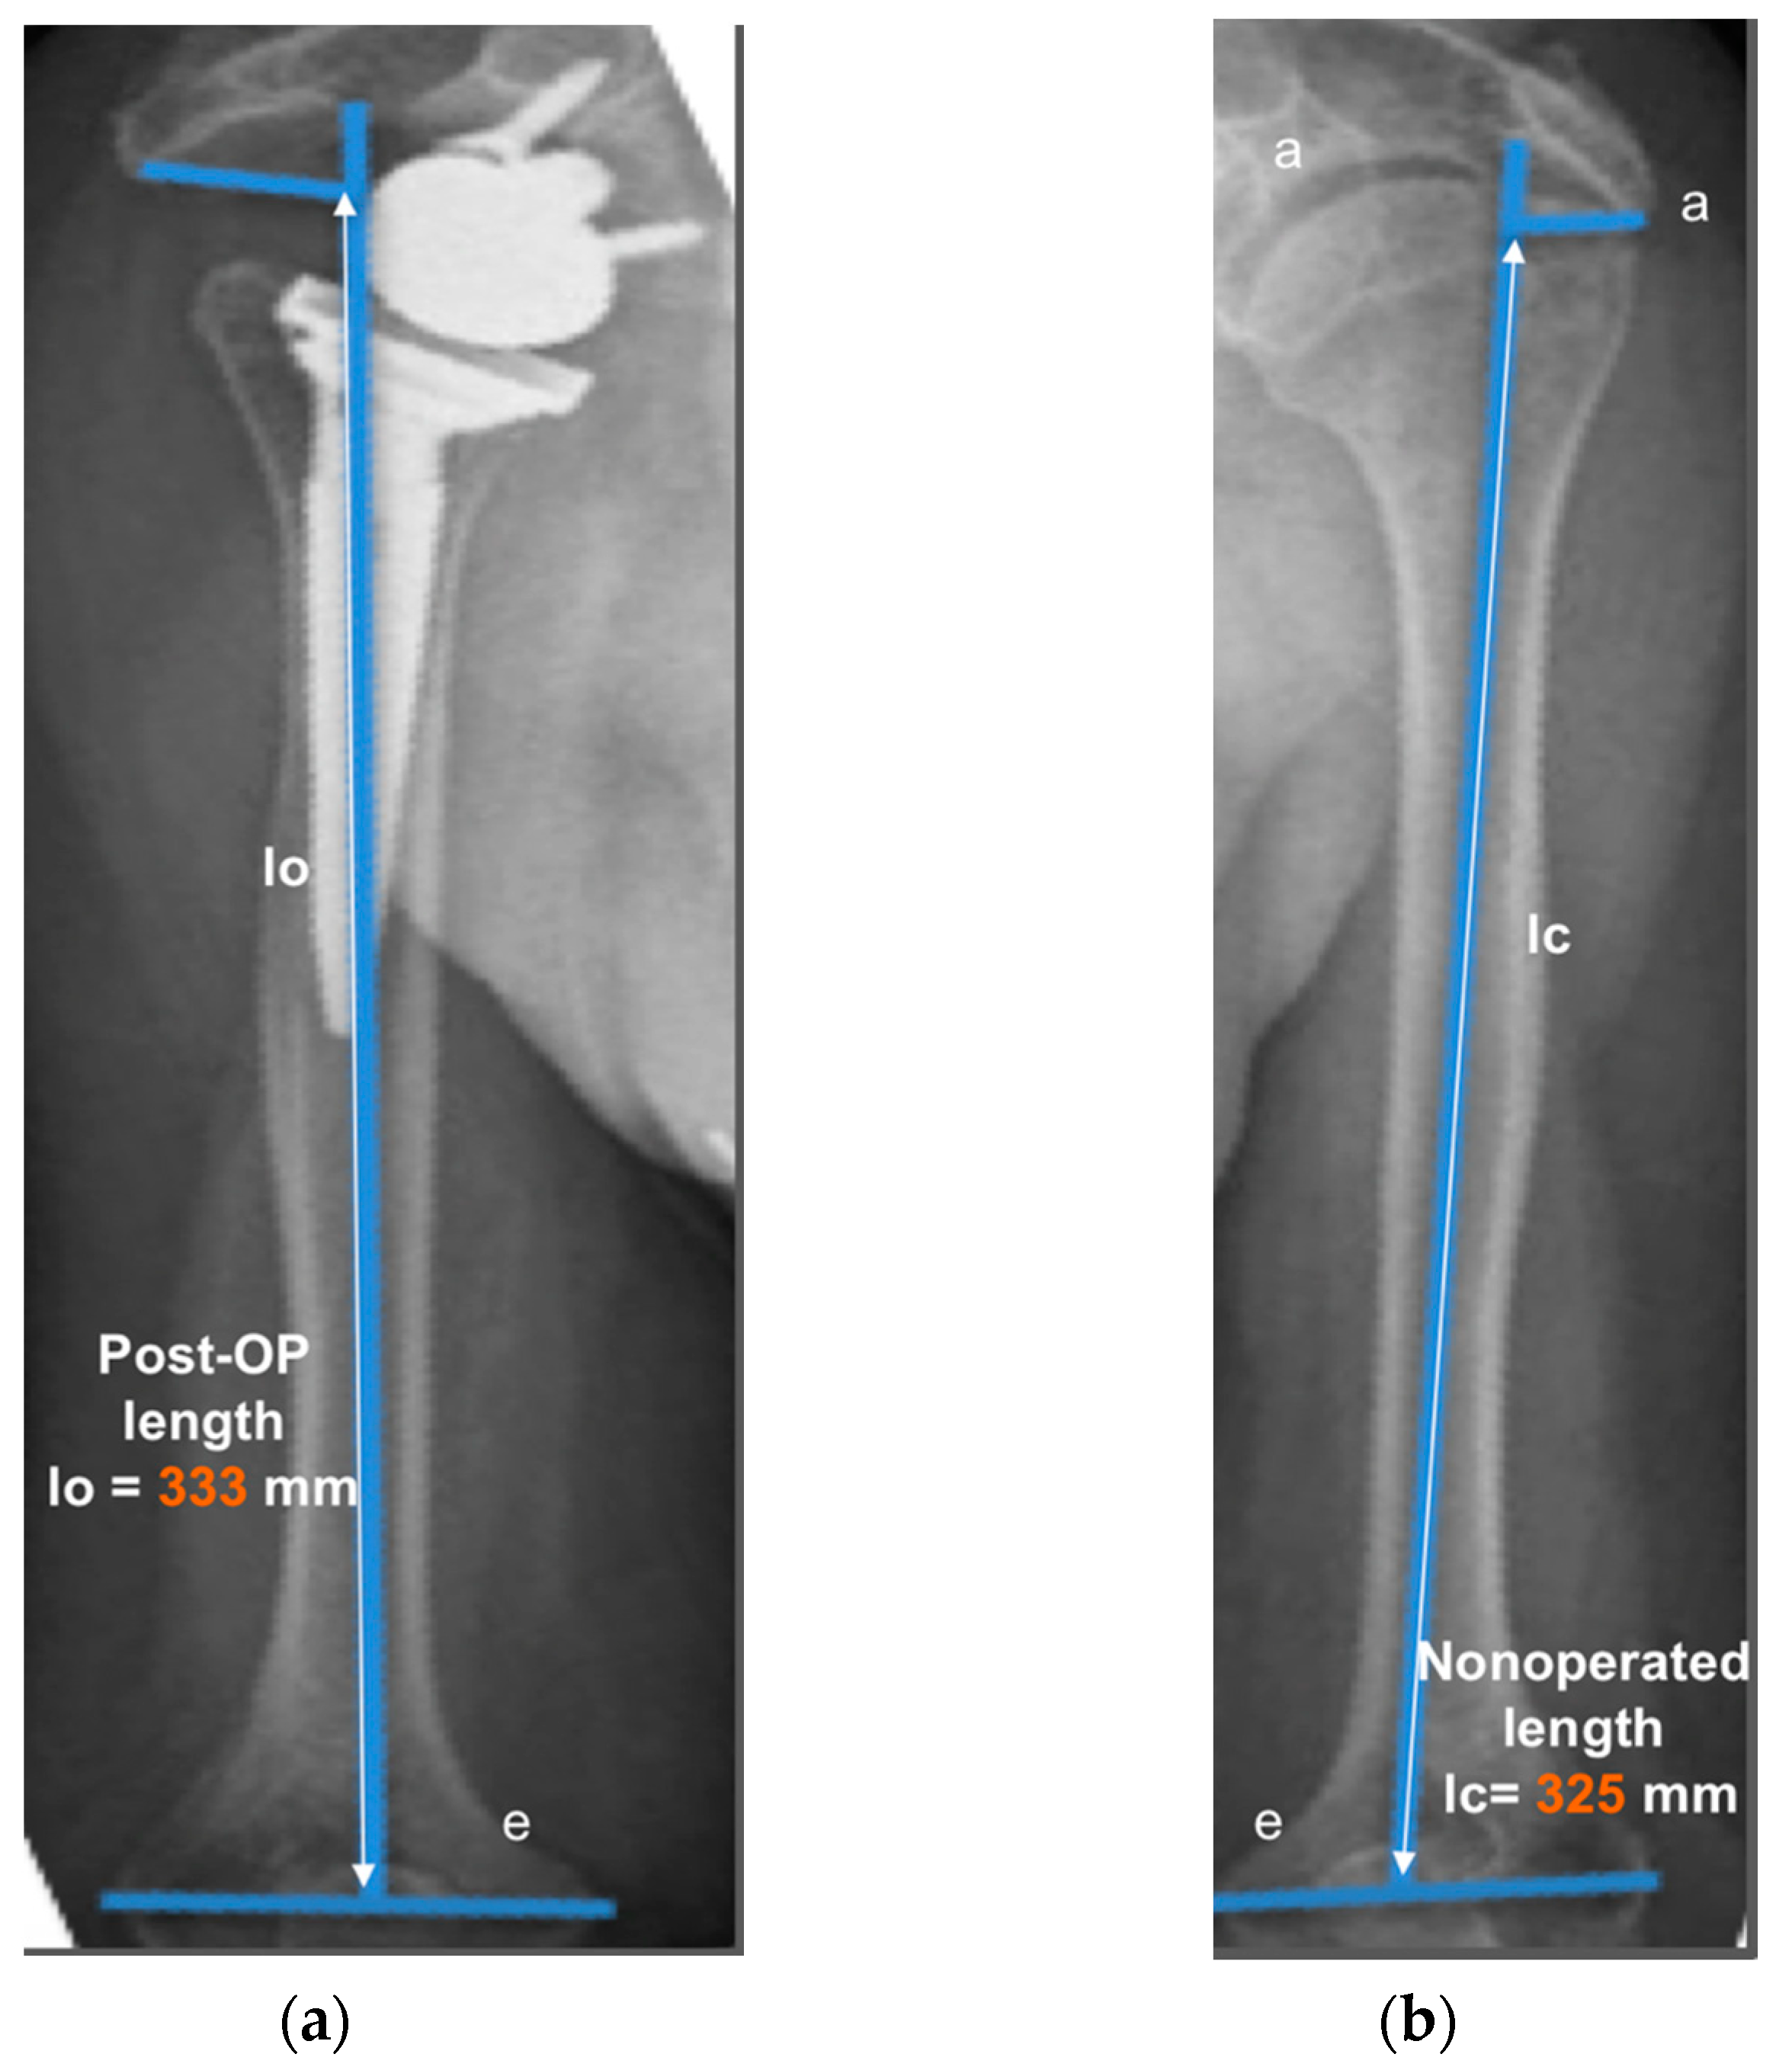

2.3. Radiographic Evaluation

- Lädermann, A.; Williams, M.D.; Melis, B.; Hoffmeyer, P.; Walch, G. Objective evaluation of lengthening in reverse shoulder arthroplasty. J. Shoulder Elbow Surg. 2009, 18, 588–595. [Google Scholar] [CrossRef]

- Lädermann, A.; Edwards, T.B.; Walch, G. Arm lengthening after reverse shoulder arthroplasty: A review. Int. Orthop. 2014, 38, 991–1000. [Google Scholar] [CrossRef]